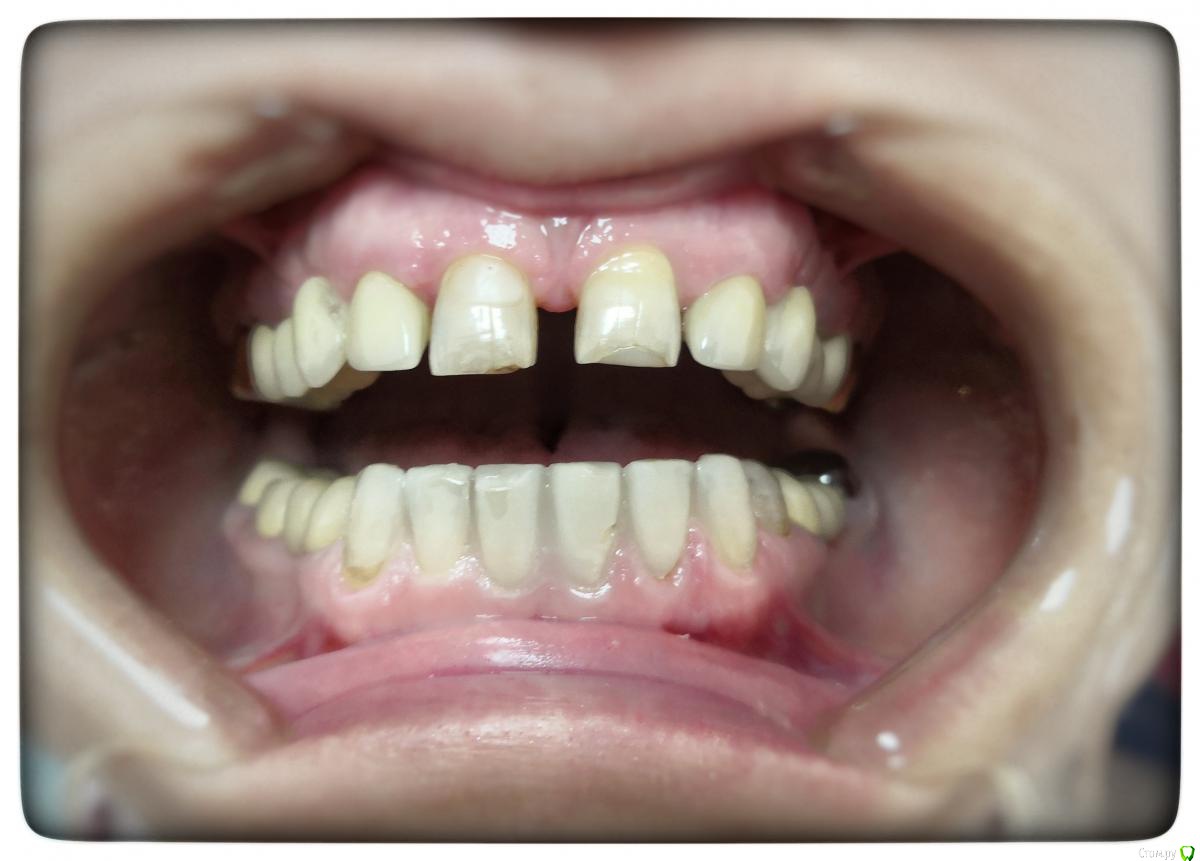

Sagaydak Aleksandr Опубликовано 27 марта, 2019 Поделиться Опубликовано 27 марта, 2019 Здравствуйте. Нужен совет более опытных коллег. Моя первая работа на e.max. Виниры от 3.3 по 4.3. Слепки не получилось снять в день обработки, повторно прокладывать нити в этот день не стал. Сделал времянки, приклеил точечно на адгезив. Назначил через неделю повторно слепки снимать. На повторном приёме пациент жалуется на чувствительность зубов от температурный раздражителей. А теперь вопросы. Должны ли зубы под времянками чувствовать холод и тепло? Будут ли они под постоянными конструкция и чувствовительны? Если будут, то что делать? Как облегчить процесс демонтажа времянок? На повторном приёме потратил на это почти час. Спасибо за внимание. Ссылка на комментарий

Sagaydak Aleksandr Опубликовано 18 апреля, 2019 Автор Поделиться Опубликовано 18 апреля, 2019 Зафиксировал виниры. Прошло 1,5 недели. Пациент отмечает продолжение чувствительны от температурный раздражителей. Фиксировал под анестезией, три часа. Под конец фиксации пациент отмечал очень сильную чувствительность, через два дня отметил небольшое облегчение. По ночам все спокойно. Назначил пасты для снижения чувствительности. Два раза обработал зубы десенсетином. Подскажите, дальше наблюдать или может все вообще переделать? Ссылка на комментарий